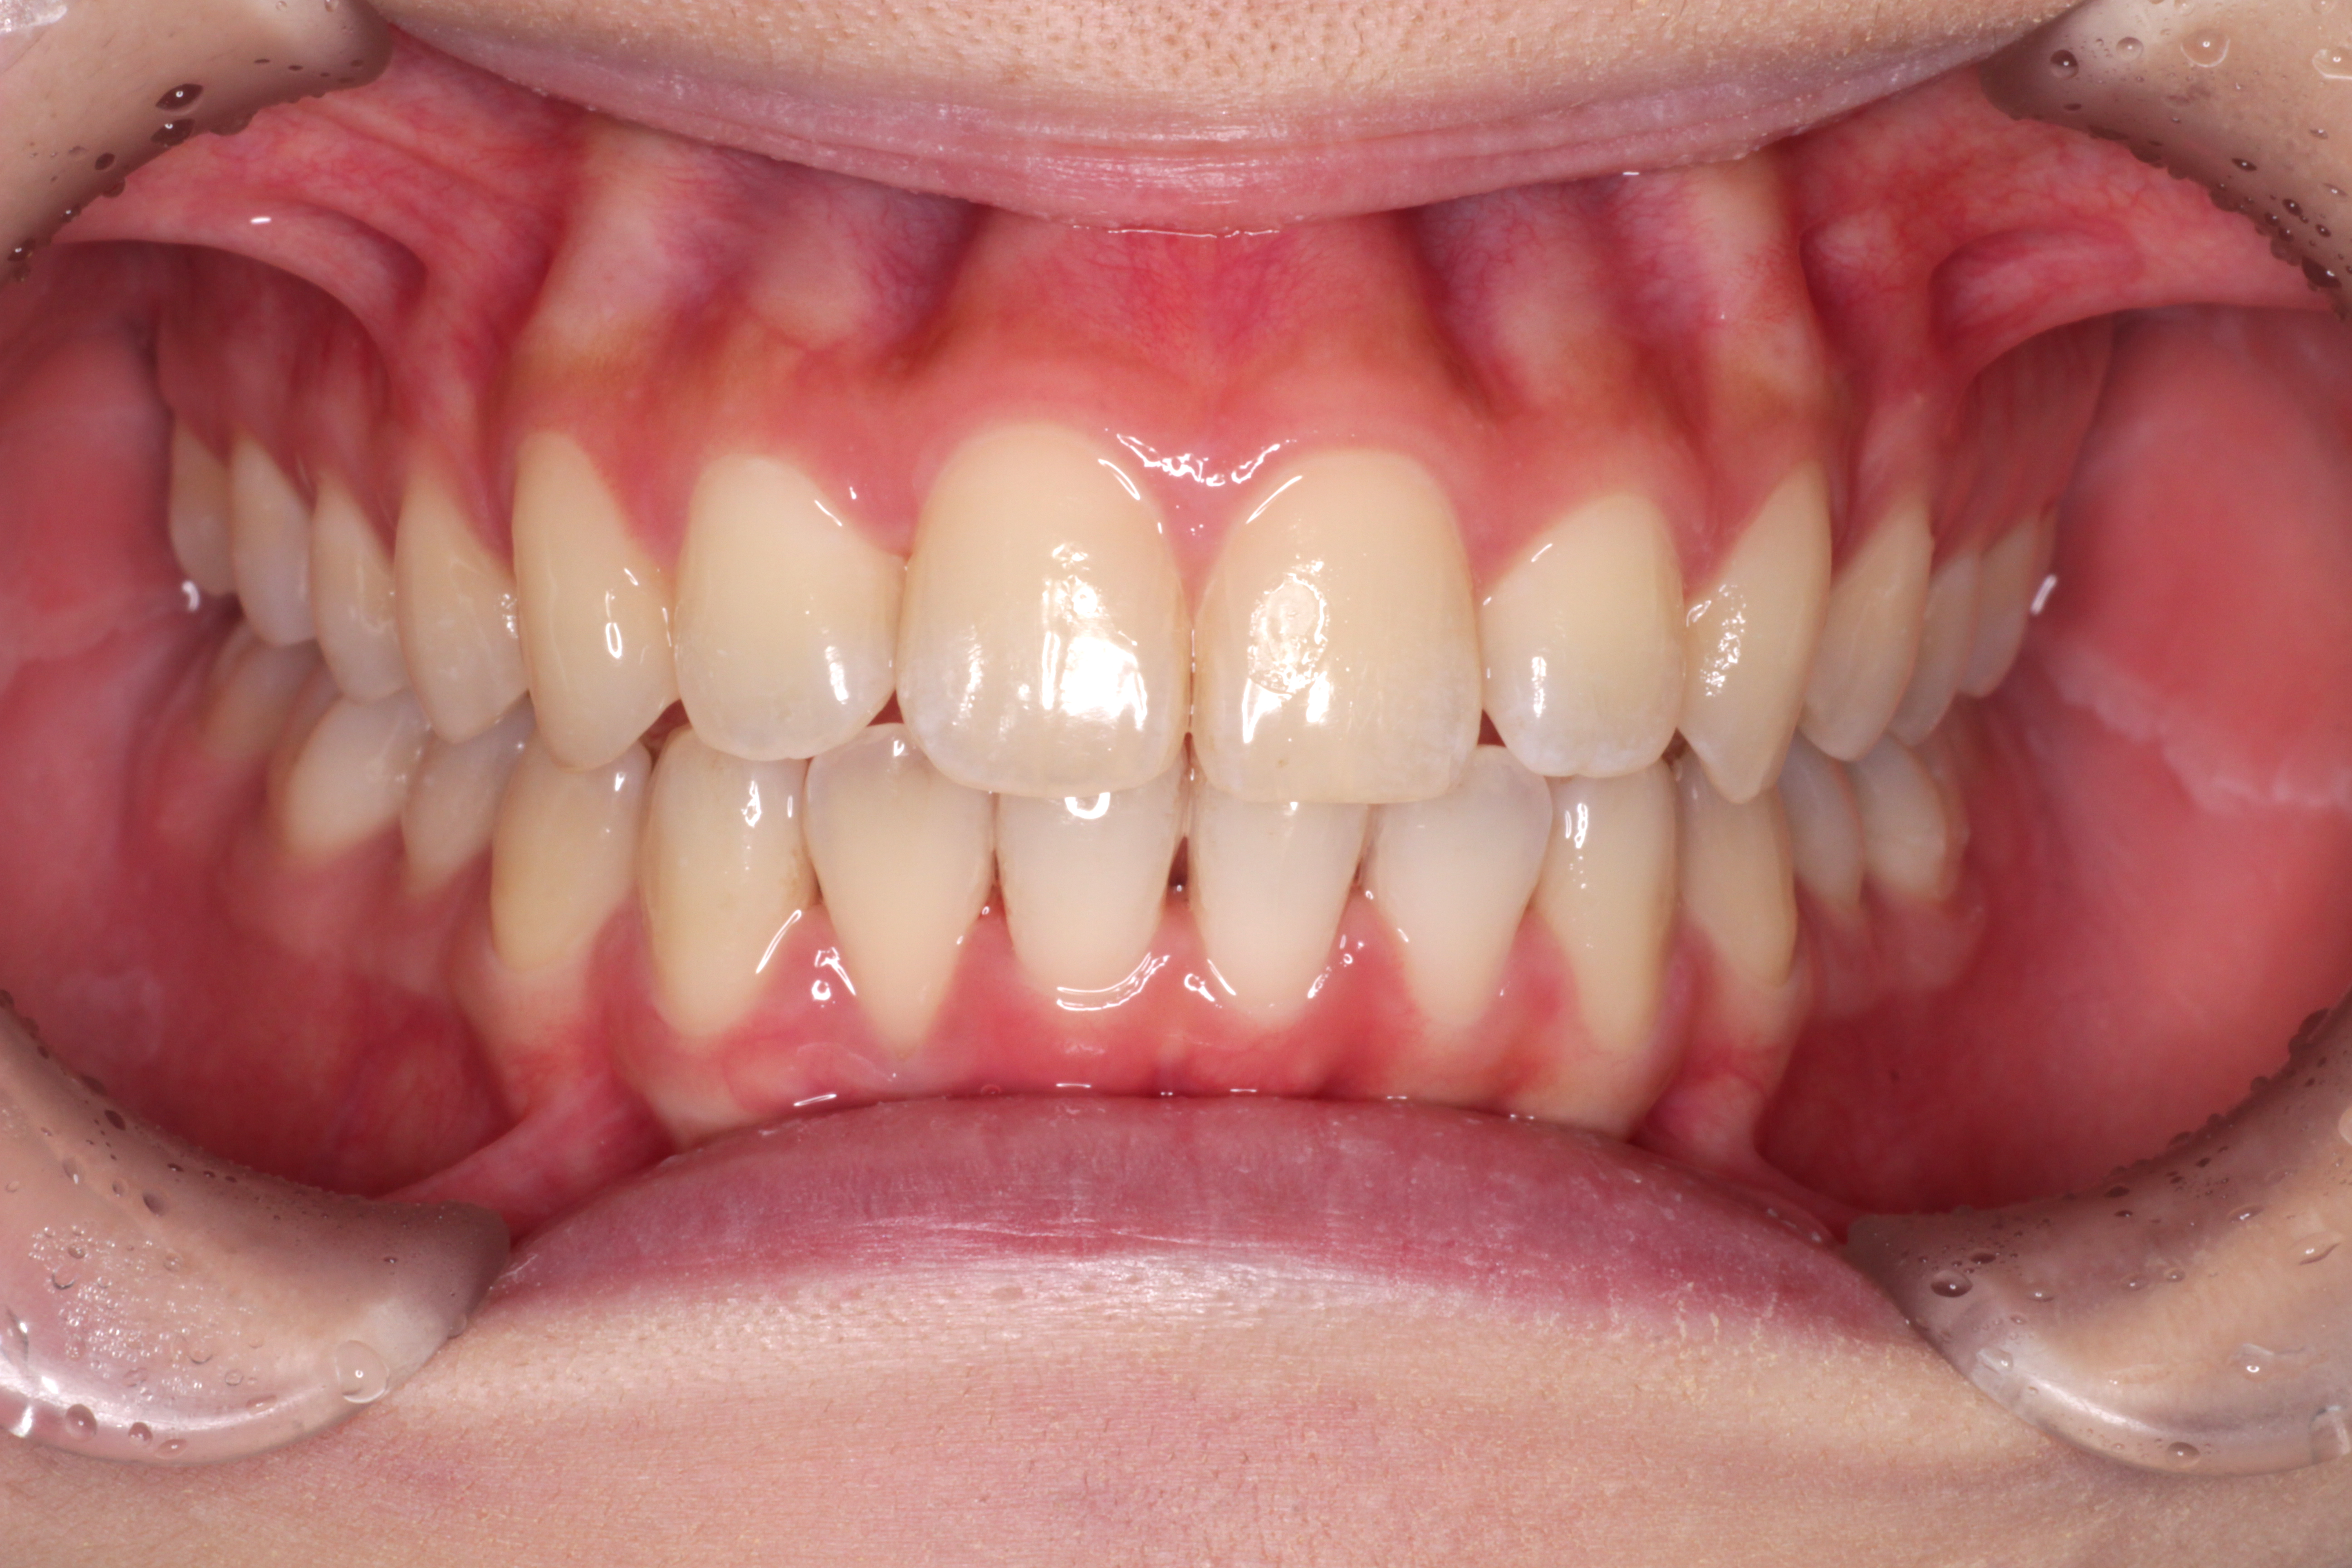

初診時のお口の中の状態です。↓

お口の中の状態としては

⑴咬み合わせが深い。(上の歯がかぶさっていて、下の歯が見えません。)

⑵右下の前から2番目の歯が叢生で歯列に入っていません。

⑶右上の前から2番目の歯が下の歯より前にありません。

診断:上顎前突・前歯部叢生